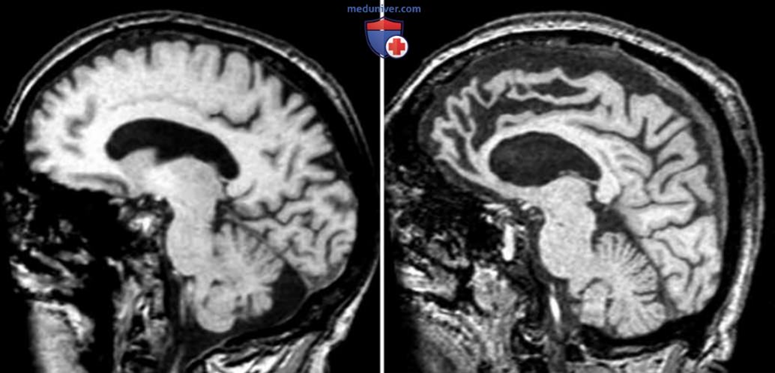

Однак інколи за такими ознаками приховується лобно-скронева дегенерація — стан, що повільно змінює роботу мозку, впливаючи насамперед на соціальну поведінку та здатність контролювати імпульси. Людина може почати діяти несподівано, говорити різко, втрачати інтерес до звичних занять, і це зазвичай помітніше для оточення, ніж для неї самої. У такі моменти важливо, щоб поряд було середовище, де відчуття безпеки та підтримки зберігаються попри зміни — саме це здатен забезпечити пансіонат для літніх людей в Києві.

На відміну від інших нейродегенеративних станів, лобно-скронева дегенерація довго не зачіпає основні рухові функції. Людина може вільно пересуватися, але з’являється повільність, менше бажання виходити надвір. Нові звички створюють «внутрішній простір», який здається зручнішим.